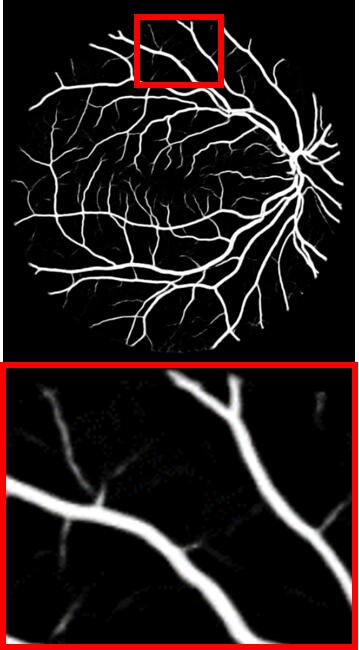

Refer to caption

(a) Input

(b) GT

(c) M-Net

(d) AG-Net

(e) BL

(f) BLST

(g) Ours

Figure 4: Example results for DRIVE. M-Net, AG-Net, and BL disregard some edge structures, which are very similar to textures. Conversely, by decomposing structures and textures, BLST gains better discrimination power and detects more tiny structures. Comparing (f) and (g), when adding the texture block, more tiny boundary structures are detected.

We remove the texture block, structure loss ssubscript𝑠{\mathcal{L}}_{s}, and texture loss tsubscript𝑡{\mathcal{L}}_{t} from STD-Net and name the baseline model as BL. The model BLST is formed by adding the structure-texture loss into BL. Fig. 4 shows a test example, including the ground truth vessel (GT) and segmentation results obtained by M-Net, AG-Net, BL, BLST, and the proposed STD-Net. The experimental results of BL and BLST are shown in Table 3.